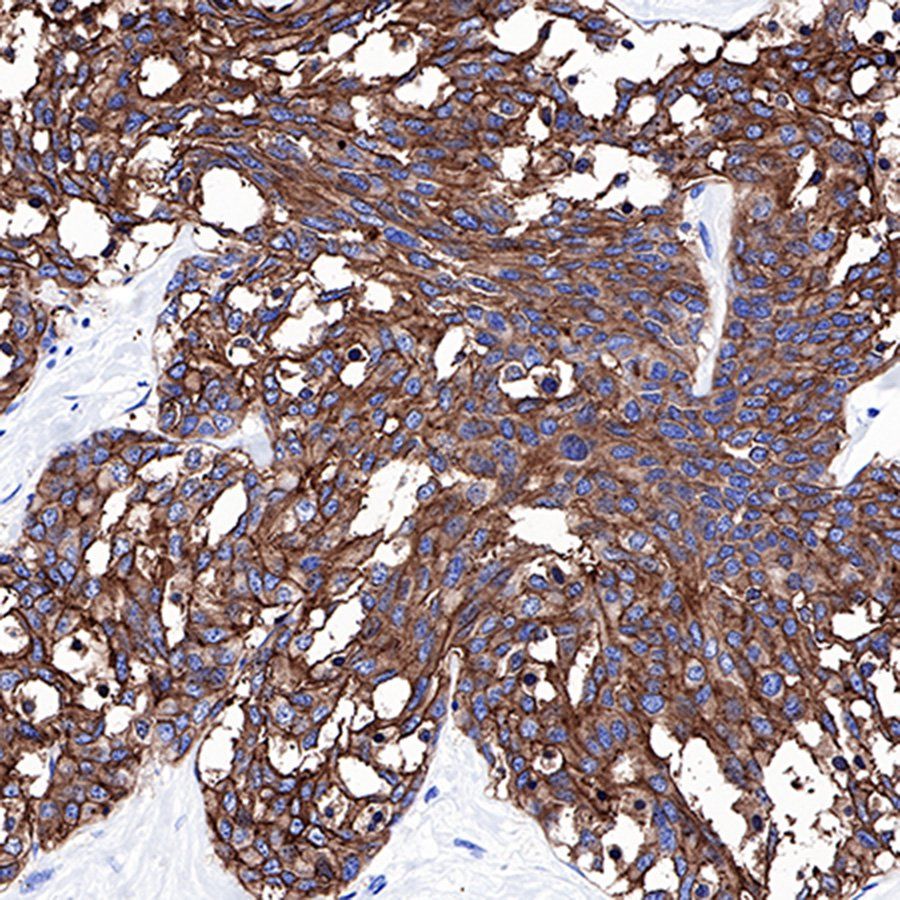

IHC shows positive staining in paraffin-embedded human lung adenocarcinoma. Anti-CEA(CD66e) antibody was used at 1/1000 dilution, followed by a Goat Anti-Rabbit IgG H&L (HRP) ready to use. Counterstained with hematoxylin. Heat mediated antigen retrieval with Tris/EDTA buffer pH9.0 was performed before commencing with IHC staining protocol.